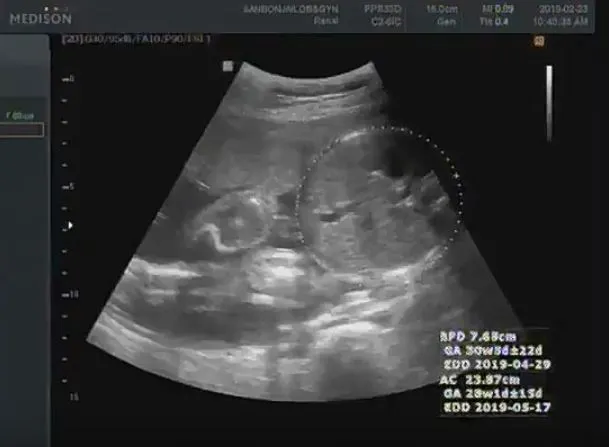

짠짠이 29주 ~ 36주 차

29 ~ 36주.

아내는 날이 갈수록 점점 배가 불러갔고 짠짠이는 엄마 뱃속이 좁다고 매일 난리다. 초음파 사진 모습도 대강 비슷해서 항상 "좁다!!!"라고 하는 것 같다. 엄마 배를 뻥뻥 차서 아내는 잠도 깨고 어떨 때는 아프기까지 했다고. 아내는 이제 정말로 몸이 무겁다는 말을 실감했다. 짠짠이는 자리를 잡아 걱정이 없는데 아내는 뭘 해도 피곤하고 몸이 붓고 뼈마디가 쑤시기 시작했다. 그래도 짠짠이가 나오기 전에 둘만의 시간을 만끽하러 무거운 몸을 이끌고 열심히 다녔다. 여러 가지 모습으로 짠짠이를 맞이할 준비를 하던 시기.